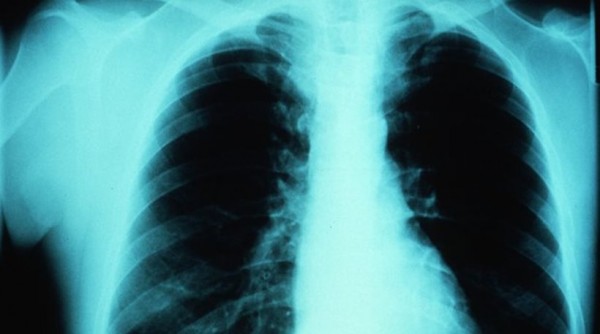

Το άσθμα είναι ένα παγκόσμιο πρόβλημα υγείας που εκτιμάται ότι επηρεάζει 300 εκατομμύρια άτομα παγκοσμίως. Είναι μία συχνή χρόνια κατάσταση που μπορεί να προκαλέσει βήχα, συριγμό, σφίξιμο στο στήθος και δύσπνοια.

Το άσθμα δεν θεραπεύεται και η φαρμακευτική αγωγή εστιάζει στην ανακούφιση των συμπτωμάτων. Τα συμπτώματα του άσθματος μπορούν να επιδεινωθούν είτε σταδιακά είτε αιφνίδια. Αυτό αναφέρεται συχνά ως «κρίση άσθματος» ή «παρόξυνση». Οι σοβαρές παροξύνσεις μπορεί να οδηγήσουν σε νοσηλεία και μπορεί να είναι απειλητικές για τη ζωή. Ωστόσο, όταν χορηγείται κατάλληλη θεραπεία, το άσθμα μπορεί να ελεγχθεί χωρίς συμπτώματα.

Υπάρχουν πολλοί διαφορετικοί τύποι άσθματος. Το σοβαρό άσθμα απαιτεί παρακολούθηση και υποστήριξη από ειδικό γιατρό. Περίπου το 5% των ασθματικών ασθενών πάσχει από σοβαρό άσθμα. Ένας ασθενής με σοβαρό άσθμα μπορεί να παρουσιάσει αναπνευστικές δυσκολίες και διατρέχει επίσης κίνδυνο σοβαρών παροξύνσεων.